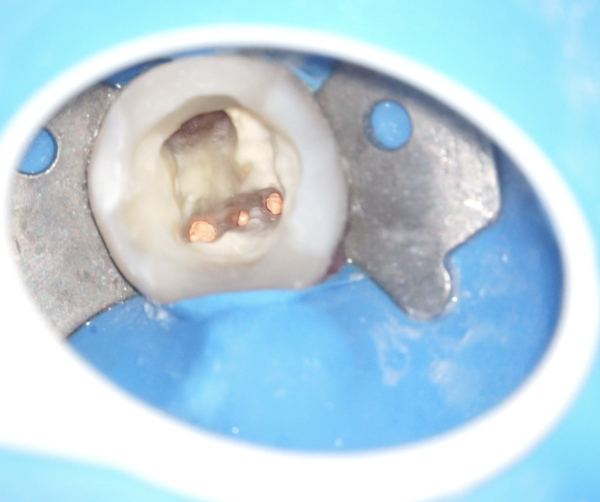

Někdy stačí málo – Praktické tipy pro zvýšení úspěšnosti v endodoncii

Během webináře si položíme otázku: Kdy je potřeba mikroskop a kdy bychom mohli zákrok zvládnout i bez něj?

Cílem je seznámit se s nejčastějšími důvody delegování na re/endodontické ošetření a komplikacemi, které při endodontickém ošetření vznikají. Řekneme si malé, ale praktické tipy, které vám mohou pomoci snížit počet delegovaných pacientů a zlepšit úspěšnost vašich zákroků.